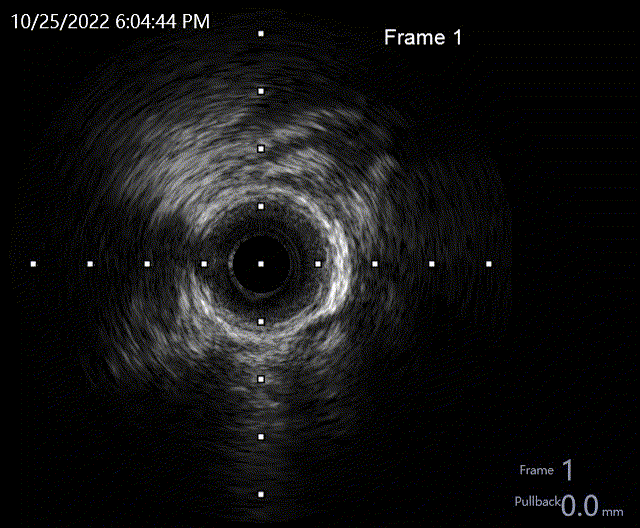

LAD IVUS-pre

沿LAD导丝送IVUS导管至LAD狭窄病变远段,检查示LAD-LM最小管腔直径1.58mm、最大管腔直径2.02mm、最小管腔面积2.4mm²,局部呈现270-360度钙化。